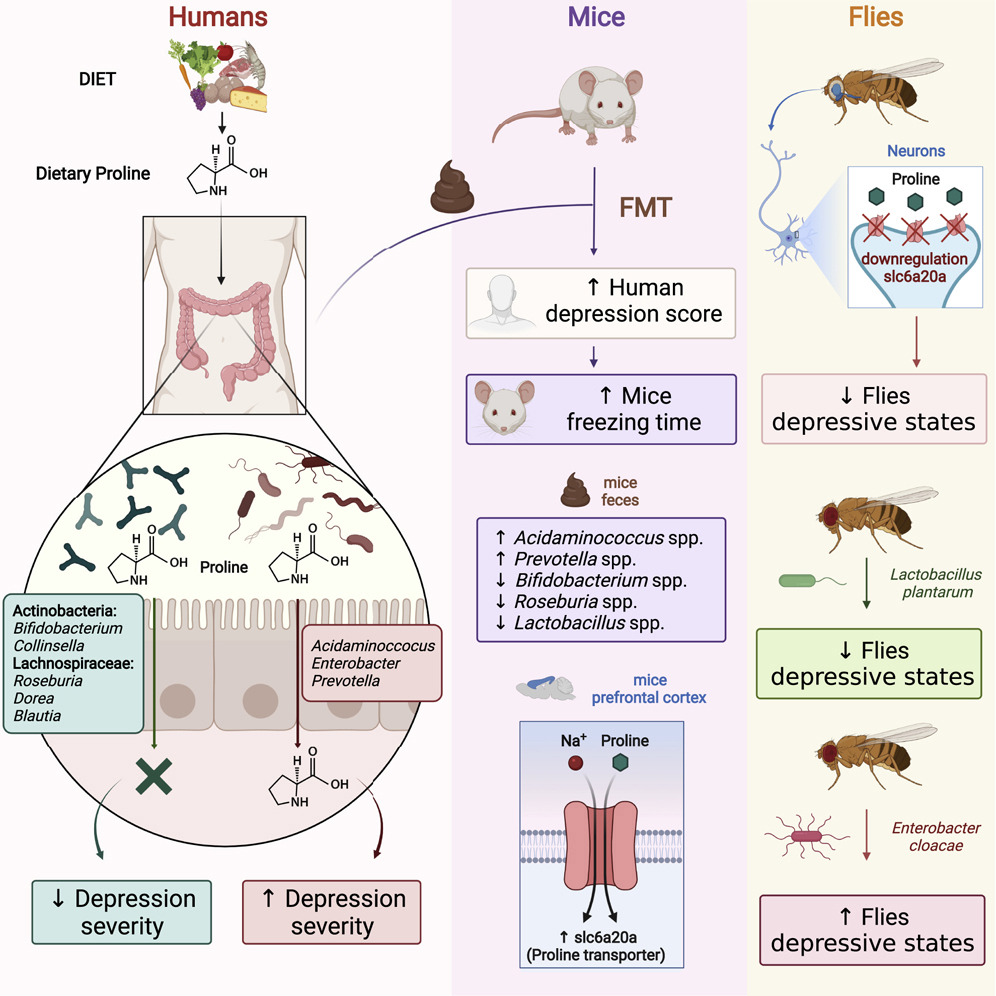

The human gut microbiome is a complex ecosystem that both affects and is affected by its host status. Zhavoronkov says this “microbiome aging clock” could be used as a baseline to test how fast or slow a person’s gut is aging

Previous analyses of gut microflora revealed associations between specific microbes and host health and disease status, genotype and diet.